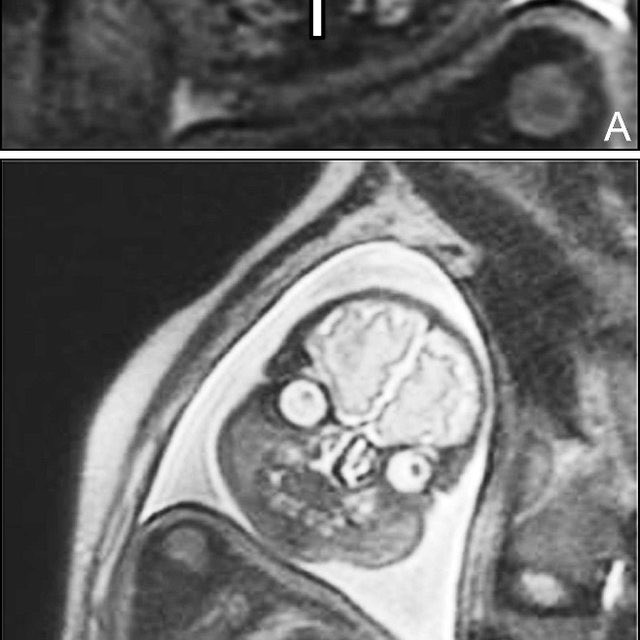

The real reason they discourage MRIs during pregnancy is because then people would realise they’re incubating nightmare demons and would be rightfully terrified ImageImageImageImage

I like how this one has its hand up like HELLO MOTHER DEAR I AM COMING FOR YOU Image

Adult face MRIs, before anyone “well actually”s me, are still kinda grim but approximately 200% less cursed than foetal ones

THIS ONE IS NEONATAL

IT HAS ESCAPED CONTAINMENT

RUN WHILE YOU STILL CAN Image

That thing that looks like a fancy moustache? That’s unerupted teeth, baby